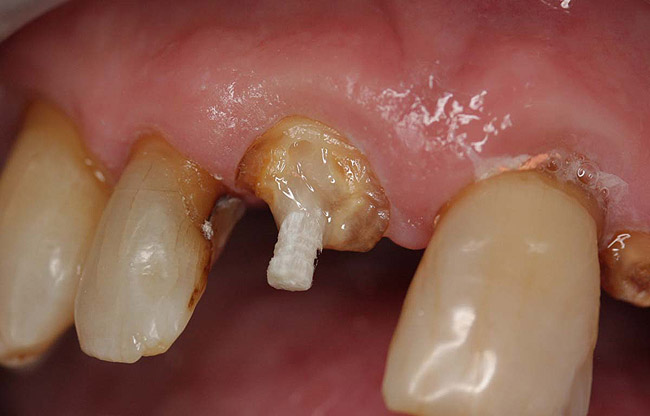

Case 4

A terminally ill patient presented an abscess on the maxillary right central incisor. Endodontic treatment was completed with a composite restoration placed to restore the access hole. The crown fractured off within 1 week (Figure 15 and Figure 16). Gutta-percha was removed, and the canal prepared to accept a C-1 white post (Figure 17). The root was bonded with BRUSH and BOND™ (Parkell, www.parkell.com) and the post was cemented with a resin cement (Figure 18). Absolute Dentin core build-up material was applied (Figure 19). There are many different build-up materials, including glass ionomers such as Ketac-Silver™ (3M ESPE, www.3mespe.com) or Miracle Mix® (GC America, www.gcamerica.com), pastes that are mixed such as Zenith (Carson Dental, www.carsondental.com), and automix syringes such as Absolute Dentin. The material was of a consistency that allows placement without sagging or running (Figure 20). It was light-cured and prepared for temporization (Figure 21) and the final all-composite restoration was delivered (Figure 22).

Figure 15  Fractured tooth in a crown of a recently treated endodontically central incisor.

Figure 15

Figure 16  The fractured central incisor root.

Figure 16

Figure 17  The root canal was prepared to accept a post.

Figure 17